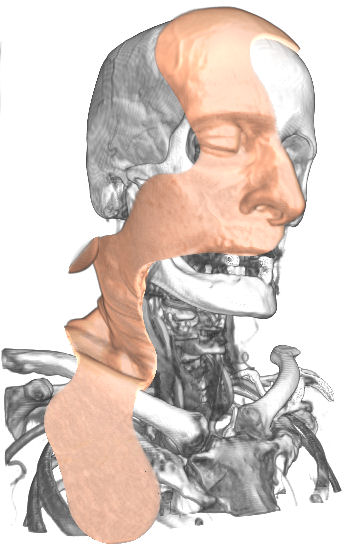

MaRRS: A Software System for Generating Multimedia Radiology Reports Using Adobe Acrobat, K. Moniz and T. McInerney, Journal of Systemics, Cybernetics and Informatics, Vol. 8, Number 3, 2010, pages 6-9.

MaRRS: A Software System for Generating Multimedia Radiology Reports Using Adobe Acrobat, K. Moniz and T. McInerney, Journal of Systemics, Cybernetics and Informatics, Vol. 8, Number 3, 2010, pages 6-9. |

MaRRS: A Software System for Generating Multimedia Radiology Reports Using Adobe Acrobat, K. Moniz and T. McInerney, The 3rd International Symposium on Bio- and Medical Informatics and Cybernetics: BMIC 2009, Orlando, FL, July 2009. Best Paper in Session Bio- and Medical Informatics and Cybernetics II, among best 10% of papers in conference and therefore selected for inclusion in Journal of Systemics, Cybernetics and Informatics |